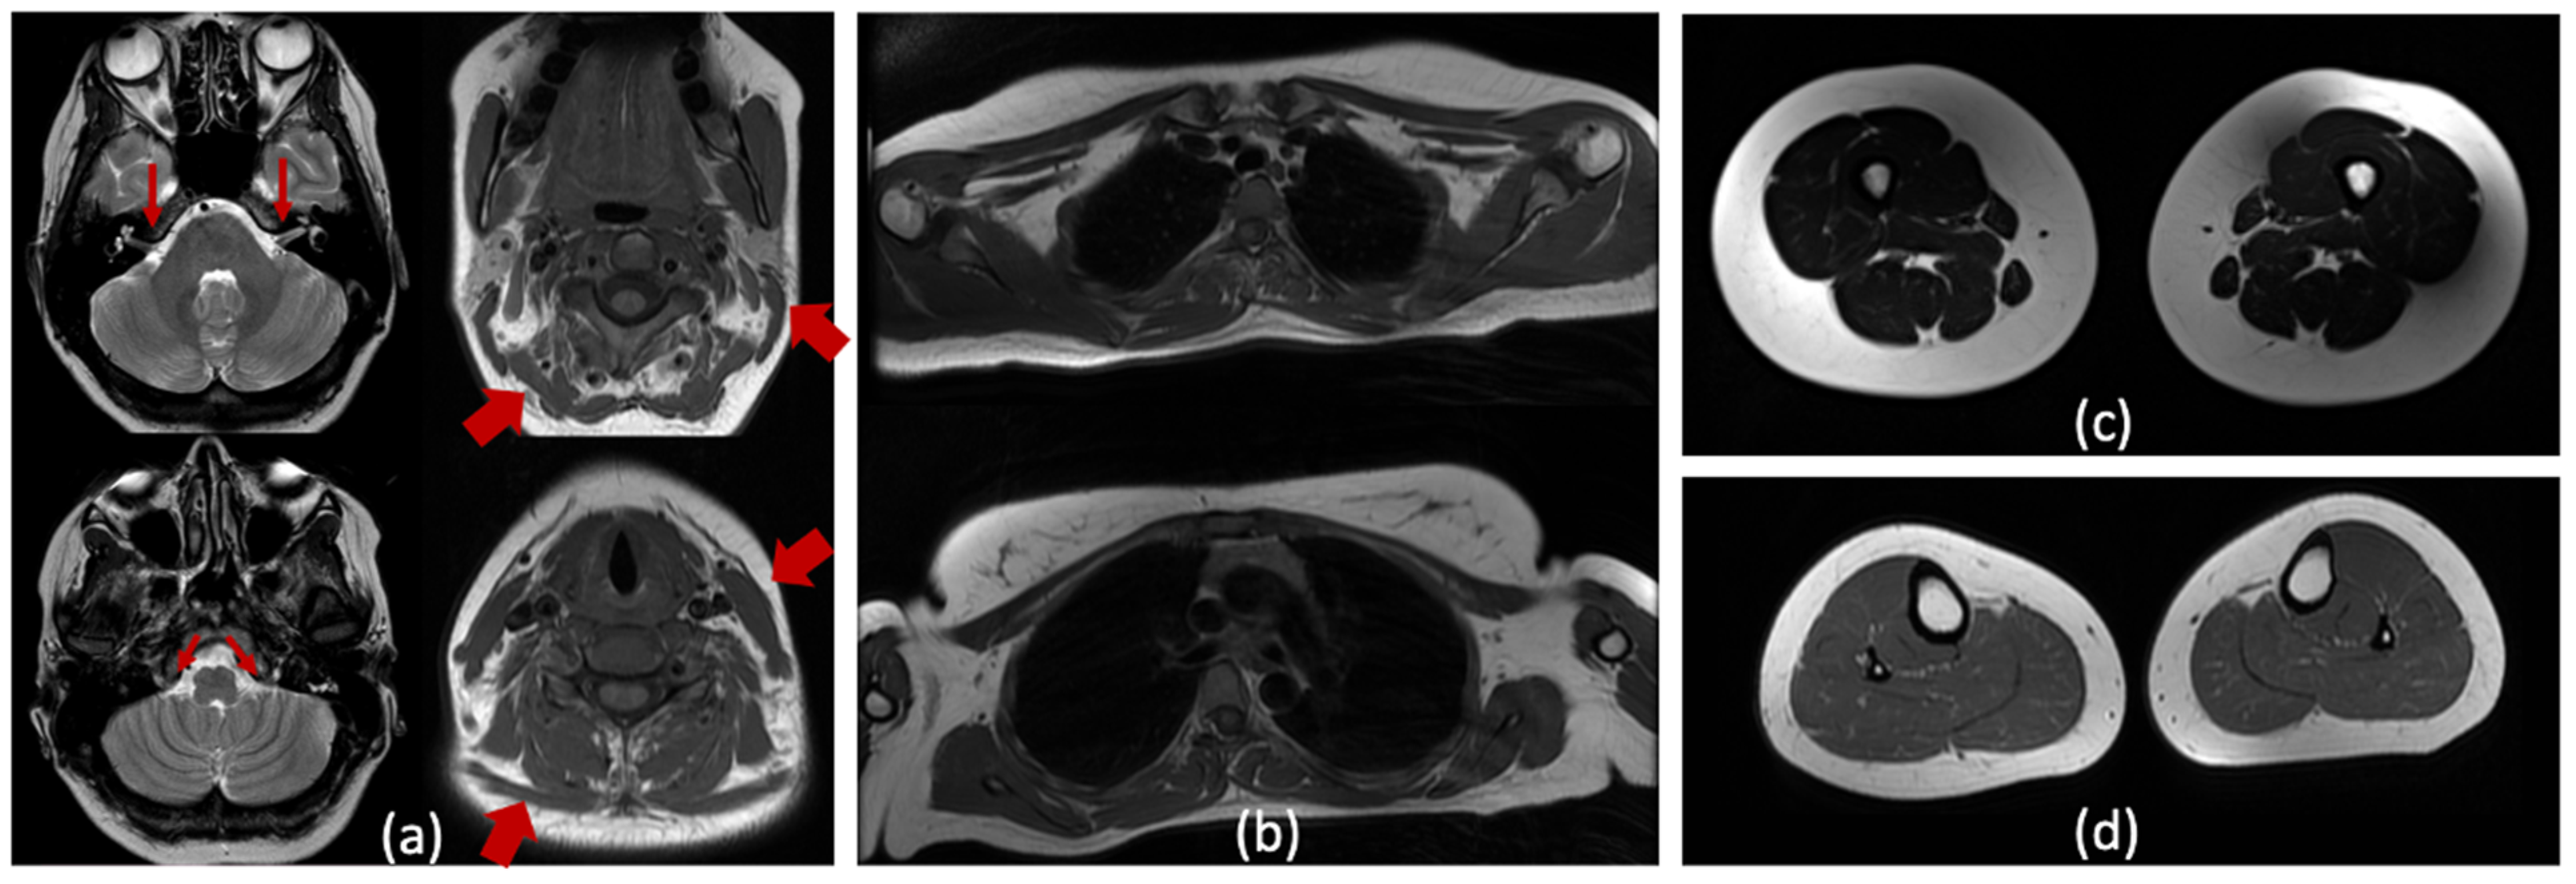

The proband underwent brain, neck and limb muscle MRI (Figure 2a–d). Cranial MRI scans revealed no structural anomalies or focal lesions; the vestibulocochlear and accessory nerves were visualized (Figure 2a). At the cervical level, mild hypotrophy of the sternocleidomastoid and trapezius muscles was observed (Figure 2a). However, it is noteworthy that the muscles of the upper and lower limbs appear unaffected on the T1- and T2-weighted images (Figure 2b–d).

Figure 2. (a) Cranial MRI (T2-WI) visualized normal vestibulocochlear and accessory nerves (narrow arrows). Some hypotrophy of sternocleidomastoid and trapezius muscles are noticed on the axial MRI (T1-WI) of the neck muscles (thick arrows); (bd) T1-WI (b,d) and T2-WI (c) imaging of the shoulder girdle and leg muscles showed no signs of skeletal muscle involvement.